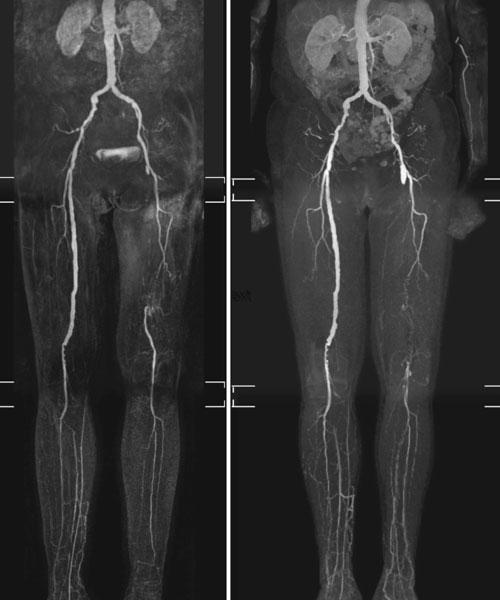

Noninvasive Angiography of Peripheral Arteries

Noninvasive angiography of peripheral arteries, used to visualize and assess the blood vessels in the arms and legs without the need for invasive procedures. These techniques provide valuable information about the health and integrity of the peripheral arterial system and help in the diagnosis and management of various vascular conditions.

Peripheral Arterial Disease

Peripheral Arterial Disease (PAD), also known as peripheral vascular disease (PVD), is a common circulatory problem in which narrowed arteries reduce blood flow to the limbs, typically the legs. PAD is primarily caused by atherosclerosis, a condition where fatty deposits (plaque) build up inside the arteries.